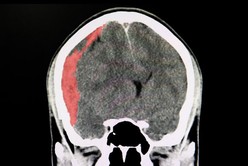

Diego Armando Maradona, actual entrenador de Gimnasia, arribó este martes por la tarde a la Clínica Olivos, donde será sometido esta noche a una cirugía a raíz de un hematoma subdural en la cabeza, luego de permanecer internado en un centro de salud de la ciudad bonaerense de La Plata.

Diego Maradona será operado por un edema en la cabeza

Según explicó su médico personal, Leopoldo Luque, quien será el encargado de llevar adelante la operación junto a su equipo, se trata de una "cirugía de rutina", por lo que Maradona "está muy tranquilo" y "de acuerdo" con la decisión, acompañado en el traslado por su hija Gianinna.